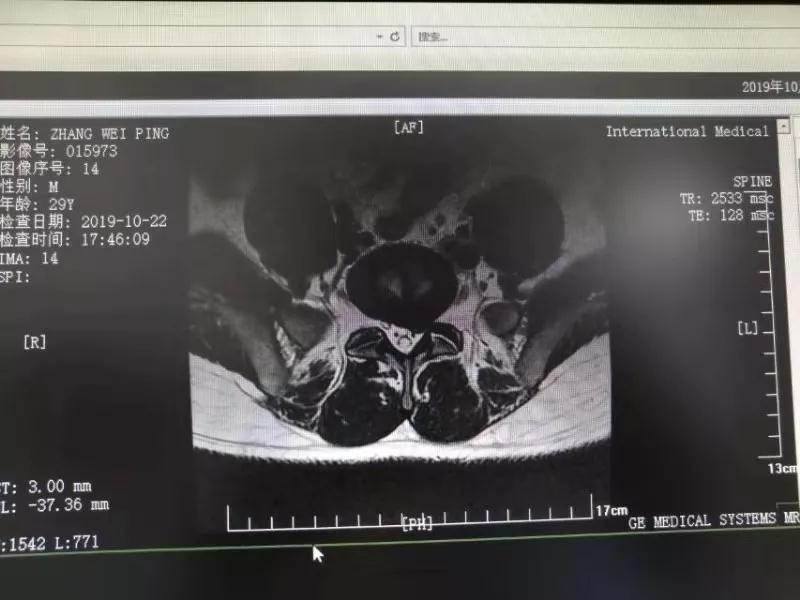

10月25日,29歲的患者小張了解到西安國(guó)際醫(yī)學(xué)中心骨科醫(yī)院專家云集,一大早便在家人的陪同下,來(lái)到西安國(guó)際醫(yī)學(xué)中心骨科醫(yī)院就診?!拔已闯掷m(xù)2年多,最近感冒后腰痛癥狀明顯加重了。”小張面露苦楚,因?yàn)殚L(zhǎng)期腰痛、左下肢放射性疼痛,她晚上睡覺(jué)不能平躺,經(jīng)常疼得睡不著,需要口服止痛藥物才能有所緩解。走路走不了多遠(yuǎn)就開始腿抽的疼,嚴(yán)重影響到工作和生活。

結(jié)合患者的檢查以及年齡情況,王自立副院長(zhǎng)推薦讓專門研究椎間孔鏡技術(shù)王雄勛主任給小張做微創(chuàng)的椎間孔鏡手術(shù)。該手術(shù)創(chuàng)傷很小,不影響脊柱的穩(wěn)定性,尤其適合于椎間盤突出的年輕患者,懷著對(duì)骨科醫(yī)院專家的信任,小張與家人商議后,接受手術(shù)治療。